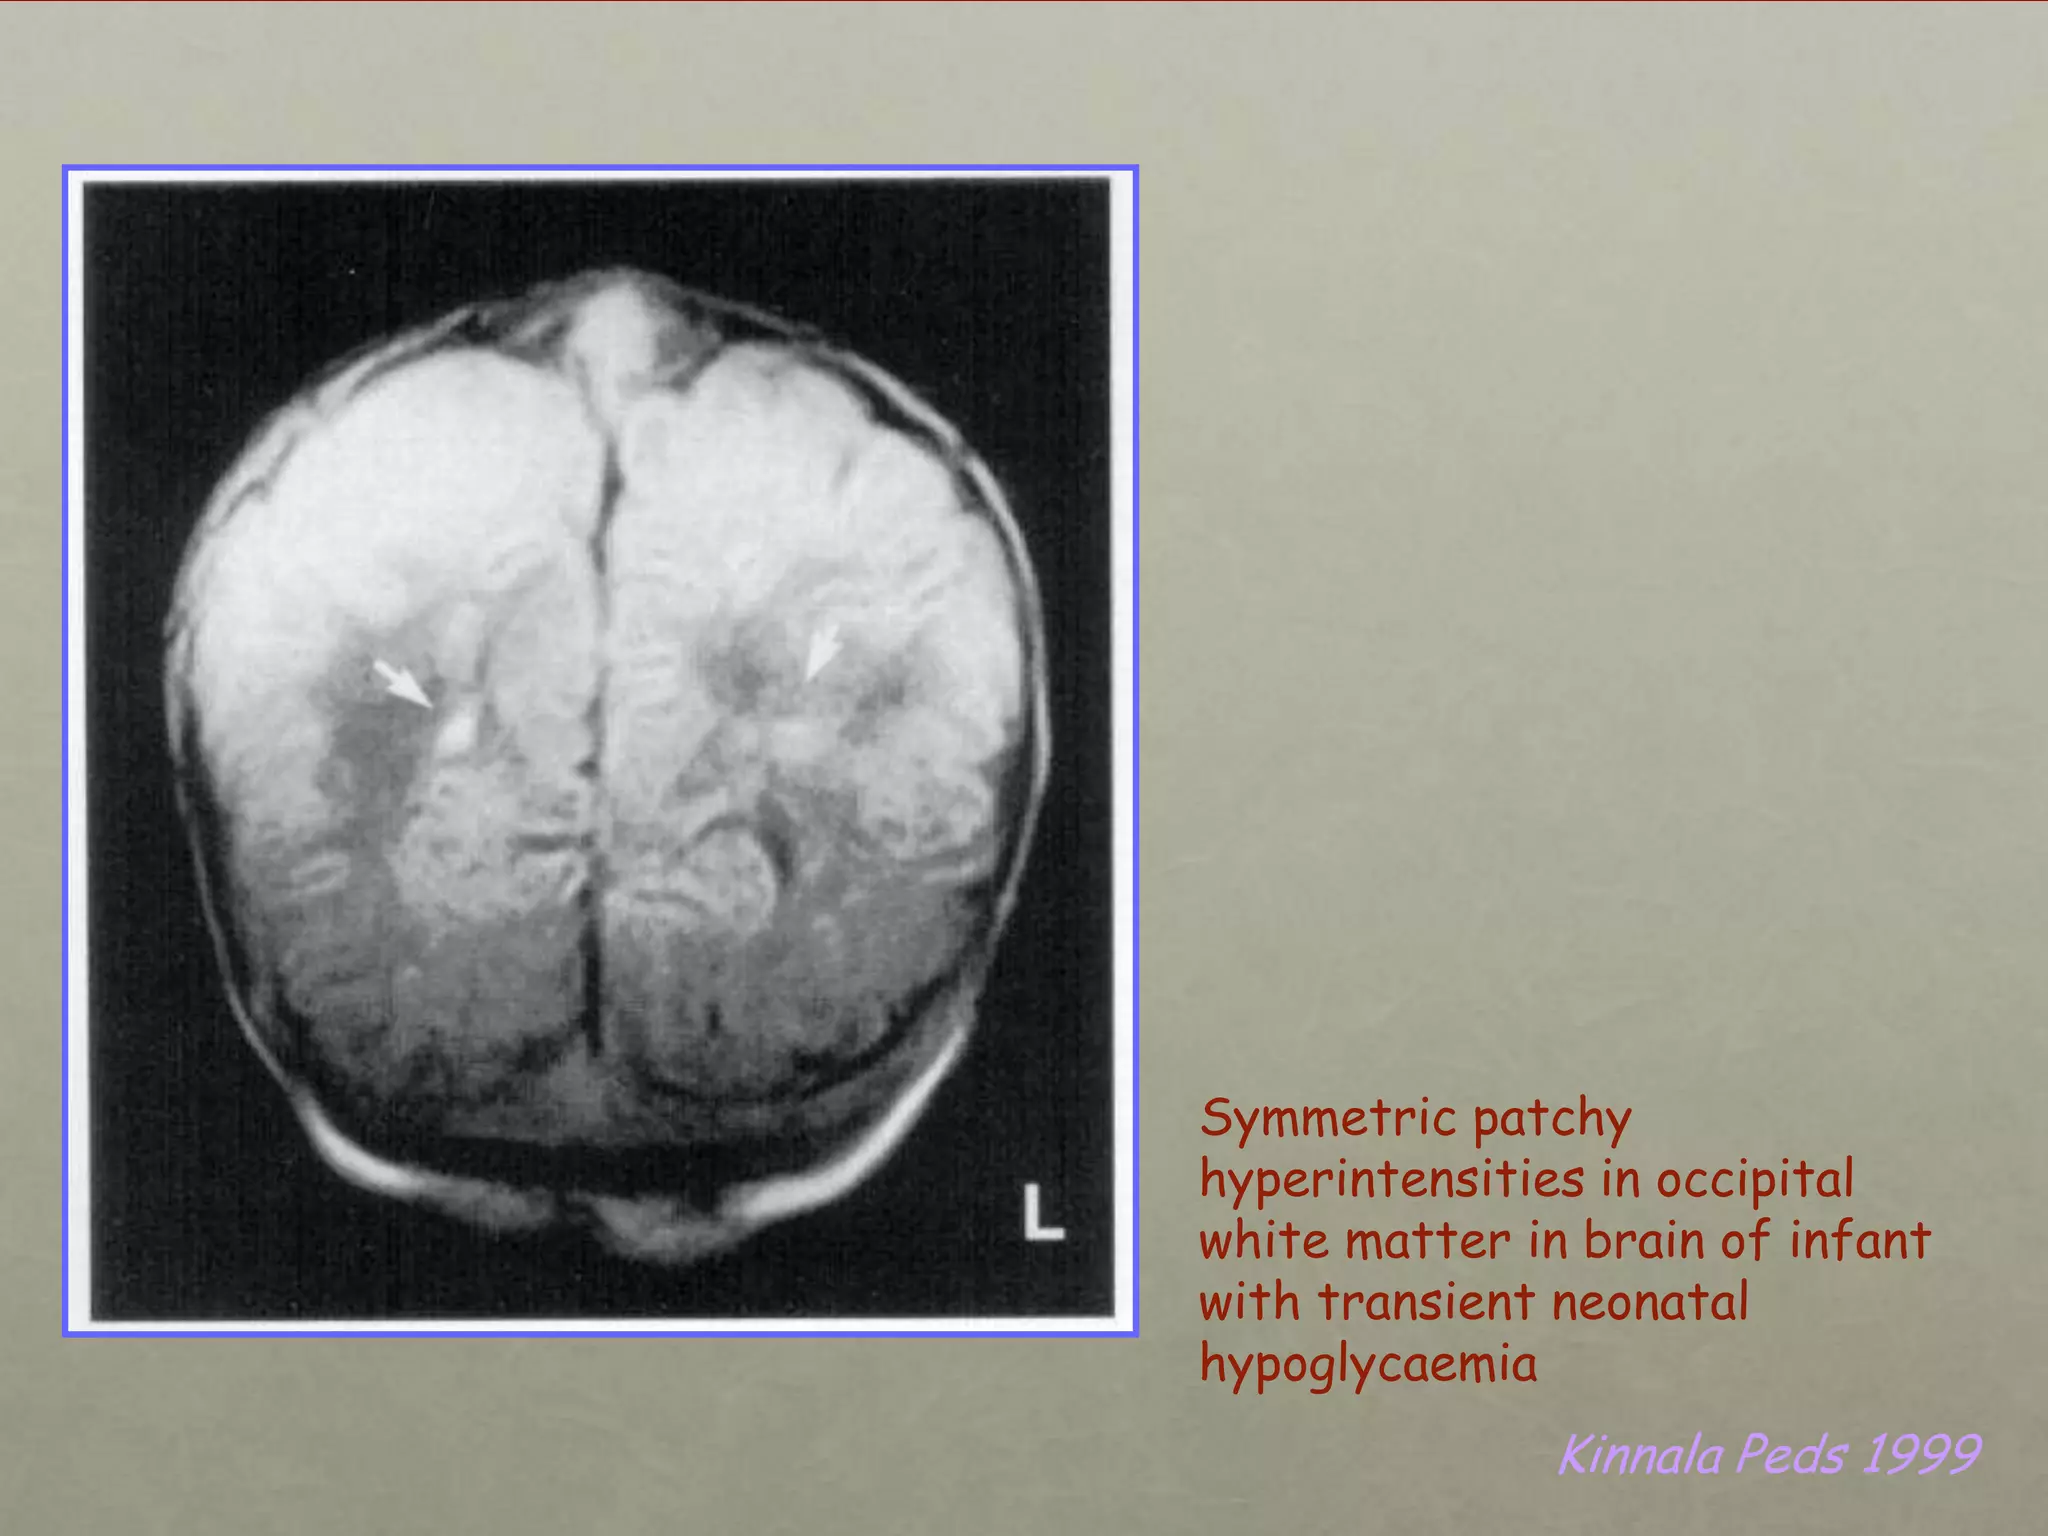

Symmetric patchy

hyperintensities in occipital

white matter in brain of infant

with transient neonatal

hypoglycaemia

Kinnala Peds 1999

Symmetric patchy hyperintensities inoccipital white matter in brain of infant with transient neonatal hypoglycaemia Kinnala Peds 1999